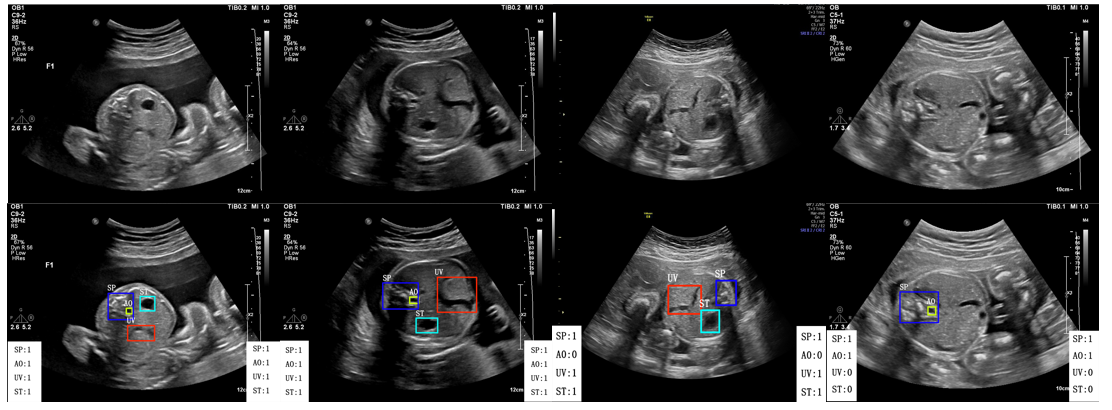

Fig. 7, Fig. 8 and Fig. 9 depict the comparison of our results with the manually labeled images by experts in the head section, abdominal section, and heart section, respectively. Our method displays the classification and detection results simultaneously to assist in sonographers’ observation. It can be seen that our method is perfectly aligned with professional sonographers.